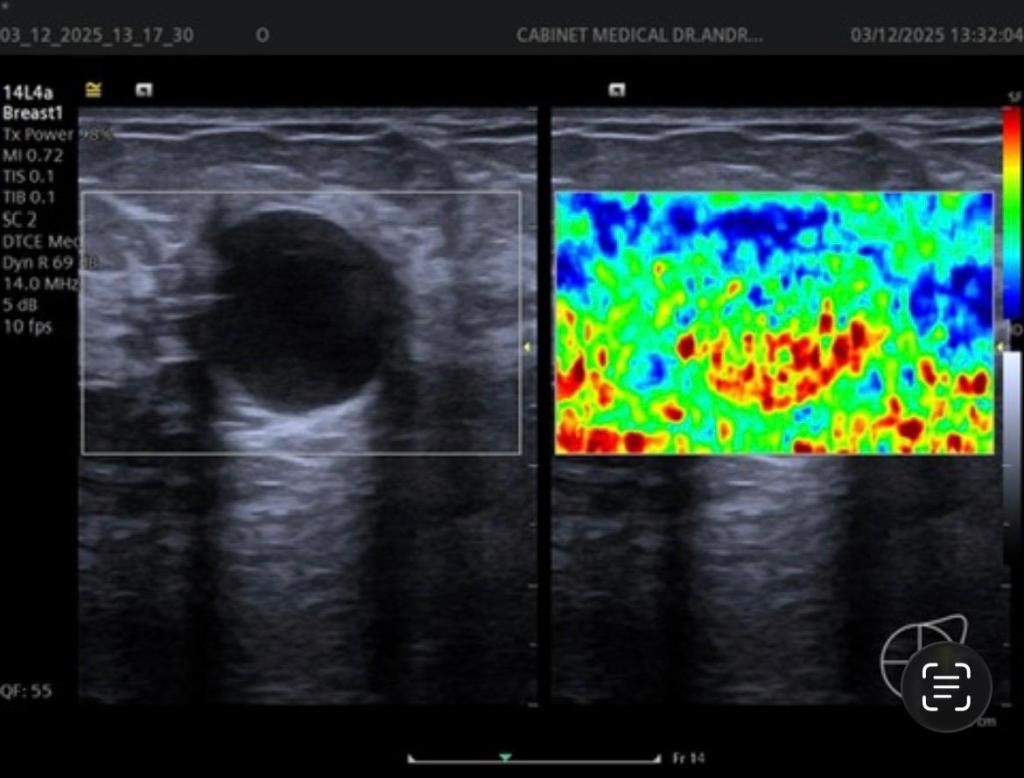

Ecografia mamară este una dintre cele mai importante metode imagistice pentru evaluarea sânului, iar atunci când este completată de elastografie, oferă informații suplimentare despre natura leziunilor.

Elastografia este o tehnică modernă care măsoară rigiditatea țesuturilor. În termeni simpli, ne ajută să „simțim” ecografic cât de dură sau moale este o formațiune mamară – similar cu ceea ce medicul încearcă să aprecieze prin palpare, dar mult mai precis.

Leziunile benigne sunt, în general, mai moi, în timp ce leziunile maligne tind să fie mai rigide. Prin elastografie, putem:

- crește acuratețea diagnosticului ecografic

- reduce numărul de biopsii inutile

- diferenția mai bine leziunile suspecte

- monitoriza evoluția unor formațiuni în timp